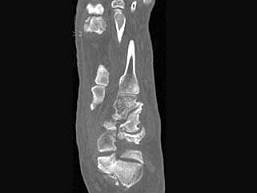

问题 男,56岁,踝关节肿胀,有糖尿病史,结合图像,最可能的诊断是?(?)

选项 A.创伤性关节炎 B.退行性关节病 C.痛风 D.类风湿关节炎 E.神经性关节病

答案 E